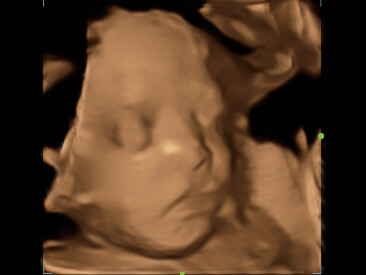

OB solution:3D/4D imaging with iLive realistic view, Smart Face and Smart OB

Clinical Images

-Fetal profile

-3D of fetal face